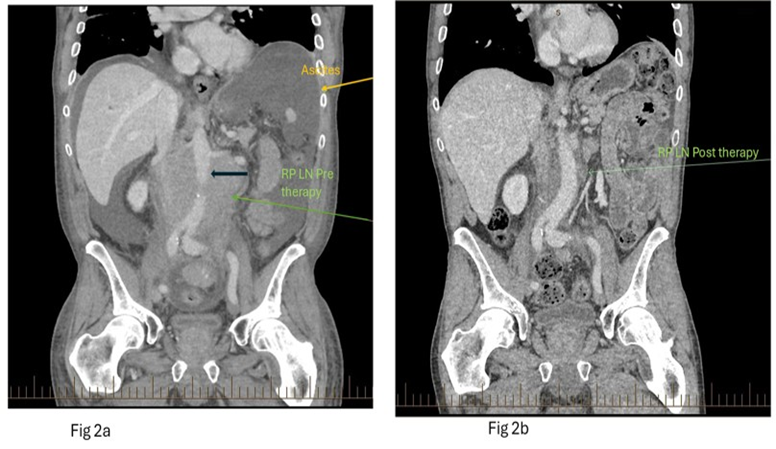

His MCL remained refractory but responded to zanirutinib therapy with an excellent clinical response, including complete resolution of his ascites. Figure 2a and Figure 2b show the pre and post treatment abdominal CT scans.

Figure 2a and 2b: Coronal contrast enhanced CT of the abdomen pretreatment (Figure 2a, left), demonstrates moderate ascites (yellow arrow) and marked soft tissue lymph nodal retroperitoneal mass (green arrow) encircling the aorta (bold black arrow). Post treatment coronal image (Figure 2b; right image) demonstrates significant reduction in the retroperitoneal mass (green arrow).